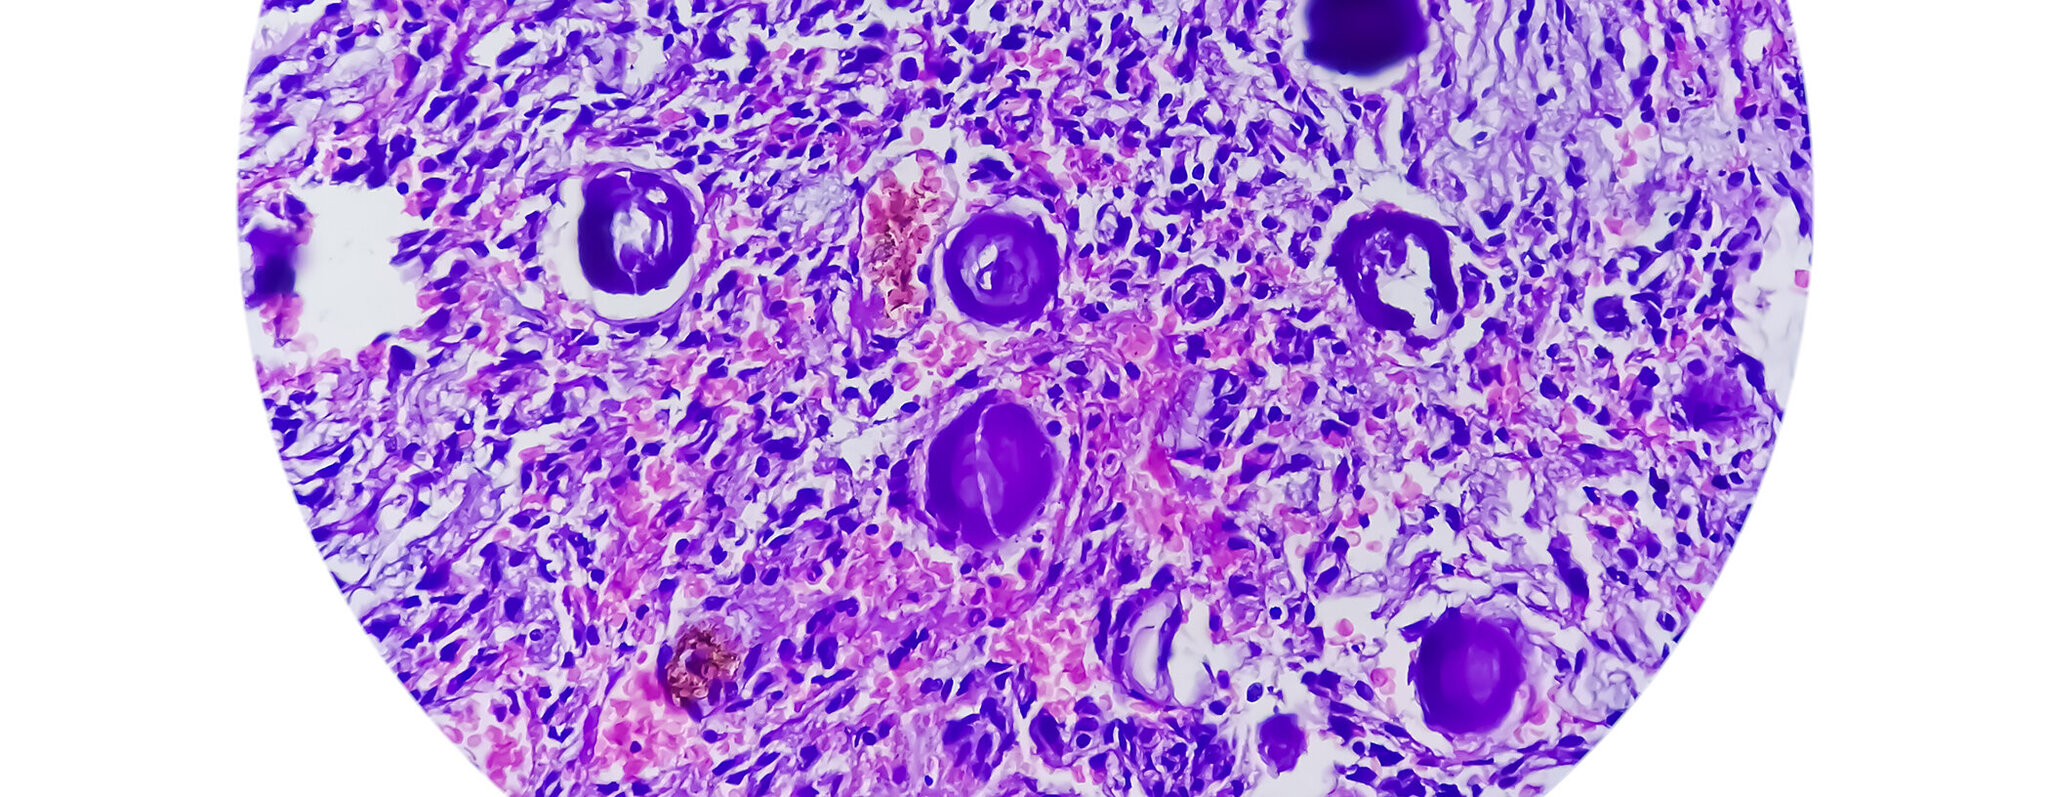

Unsere Fachärztinnen und Fachärzte versorgen alle Formen gutartiger und bösartiger Neubildungen des Knochen- und Weichgewebes sowohl konservativ als auch operativ. Wöchentliche Sarkomkonferenzen helfen uns dabei, die hoch spezialisierte Behandlung interdisziplinär zu organisieren und laufend auf dem neuesten Stand der Wissenschaft zu halten.

Im Fachbereich Tumororthopädie führen wir rund 300 Operationen pro Jahr durch. Das betrifft bösartige und gutartige primäre Neubildungen des Knochen- und Weichgewebes sowie Metastasen. Neben unserer jahrelangen Erfahrung und der außerordentlichen Spezialisierung stellen wir das hohe Niveau durch modernste Technik für unsere Patientinnen und Patienten sicher.

In der Klinik für Orthopädie und Orthopädische Chirurgie am UKS decken wir das gesamte Spektrum der operativen orthopädisch-onkologischen Eingriffe ab. Dazu gehört auch die Entfernung ausgedehnter Tumoren sowie Implantationen von sogenannten Mega-Endoprothesen, die große Segmente von Knochen und umgebenden Geweben ersetzen und damit zum Erhalt von Armen, Beinen, Becken- oder Wirbelsäulensegmenten bei bösartigen Knochentumoren wie Osteosarkom, Chondrosarkom oder Ewing-Sarkom sowie bei Metastasen beitragen.